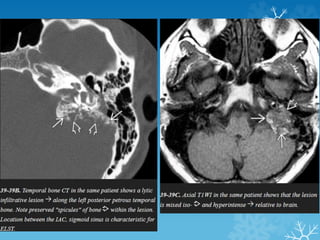

CT MRI

Endolymphatic sac tumors (ELSTs)